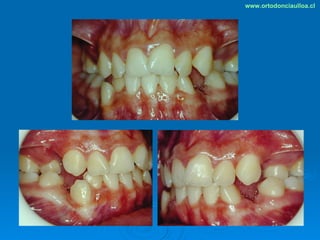

Este documento presenta dos casos clínicos de pacientes que recibieron tratamiento de ortodoncia. El primer caso fue de una paciente femenina de 14 años con apiñamiento dental y mordida cruzada que fue tratada mediante extracción de premolares y alineamiento dental. El segundo caso fue de un paciente masculino de 14 años con clase II esqueletal y desarmonía dentomaxilar que fue tratado con extracción de premolares y corrección de mordida. Ambos casos mostraron mejoría después de 3 años de tratamiento.